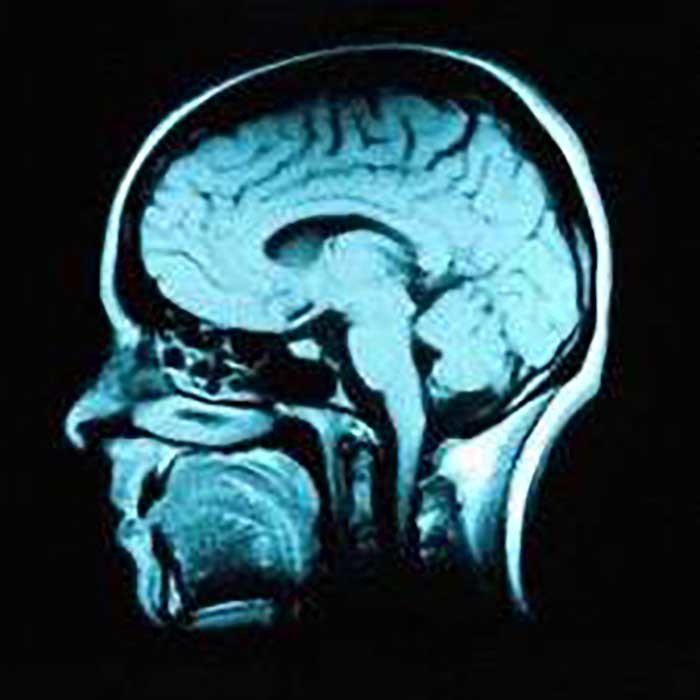

Neural membrane's structural instability may trigger multiple sclerosis